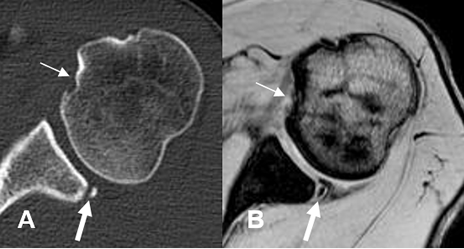

Fig 72 C. Lesión Bankart óseo y Hill Sachs invertido.

A: TAC axial y B: RM axial en FFE T2. Aplanamiento de la parte anteromedial de la cabeza humeral, por lesión de Hill Sachs invertido. (Flechas delgadas). Adicionalmente hay defecto óseo en la parte posterior de la glenoides, por lesión de Bankart invertido.(Flechas gruesas).